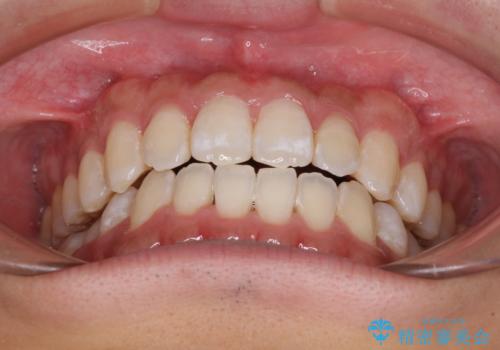

下顎前歯と上顎の部分矯正

- 上下の前歯の叢生を気にして来院された患者様です。

前歯のみの矯正治療を希望でしたが、上顎臼歯が舌側転位していたため、上顎は全体を、下顎は前歯のみを矯正治療することとしました。

矯正治療は上下全顎を行うことが大前提ですが、費用などの点から、今回は部分矯正を選択することとなりました。

患者様本人は咬みにくさを感じていないようですが、部分矯正は咬み合わせの改善が困難であることが多く、咬みにくさが残ることがあります。